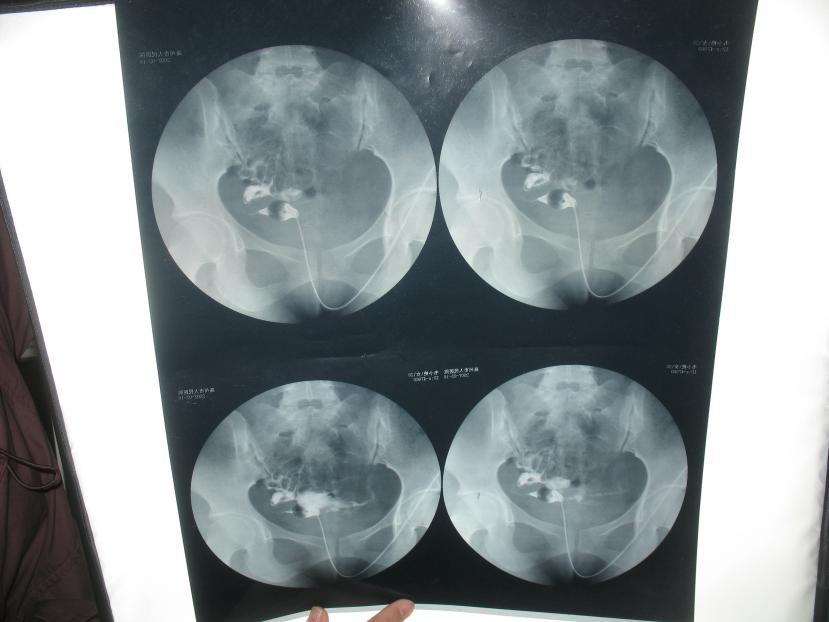

食用前:

2009年因支原体感染致双侧输卵管梗阻,之前在平果县人民医院治疗1年多,效果欠佳,后来经朋友介绍在武鸣县外院就诊。诊断:双侧输卵管梗阻处理:多肽蛋白片(天然水蛭素)2#   Tid * 30    阿奇霉素、中药通水方(加减)